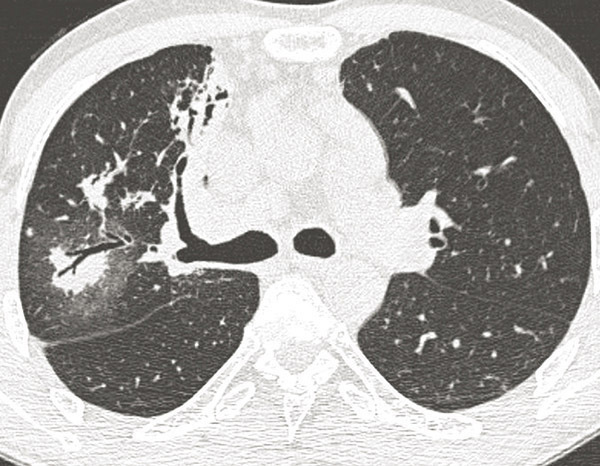

© Sylvain Poirée - La Revue du Praticien Tomodensitométrie thoracique en coupes millimétriques, en inspiration, montrant un nodule entouré d'hyperdensités en verre dépoli (signe du halo).